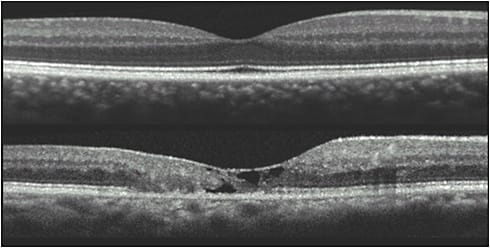

In addition to the presence of perifoveal telangiectatic vessels that leak on fluorescein angiography, other characteristic lesions of MacTel include loss of retinal transparency, crystalline deposits, a decrease or absence of the macular pigment and presence of RPE hyperplasia (Figure 1). Important diagnostic features are found on spectral-domain coherence tomography (OCT) imaging. These include disruption of the photoreceptor inner segment–outer segment junction (IS/OS) line or ellipsoid zone (EZ) and hyporeflective cavities in both the inner and outer retina (Figure 2).1

The characteristic presence of bilateral lesions of photoreceptor disruption that begin temporal to the fovea expand to generate bilateral nasal scotomas as well. A study correlating these visual field defects detected by microperimetry with OCT shows that the defects are closely associated with cavitation of the outer retina, indicating that loss of vision in MacTel is associated with structural changes at the level of photoreceptors.6 Photoreceptor abnormality occurs early in the disorder and progression of photoreceptor cell loss may be detected on OCT with defects in the EZ. This measurement of the missing EZ captured as en face images have been used as an outcome measurement in phase 1 and 2 studies of MacTel.7 These OCT abnormalities coincide with areas of functional deficits found on microperimetry, providing a structure–function correlation in this ocular condition.7